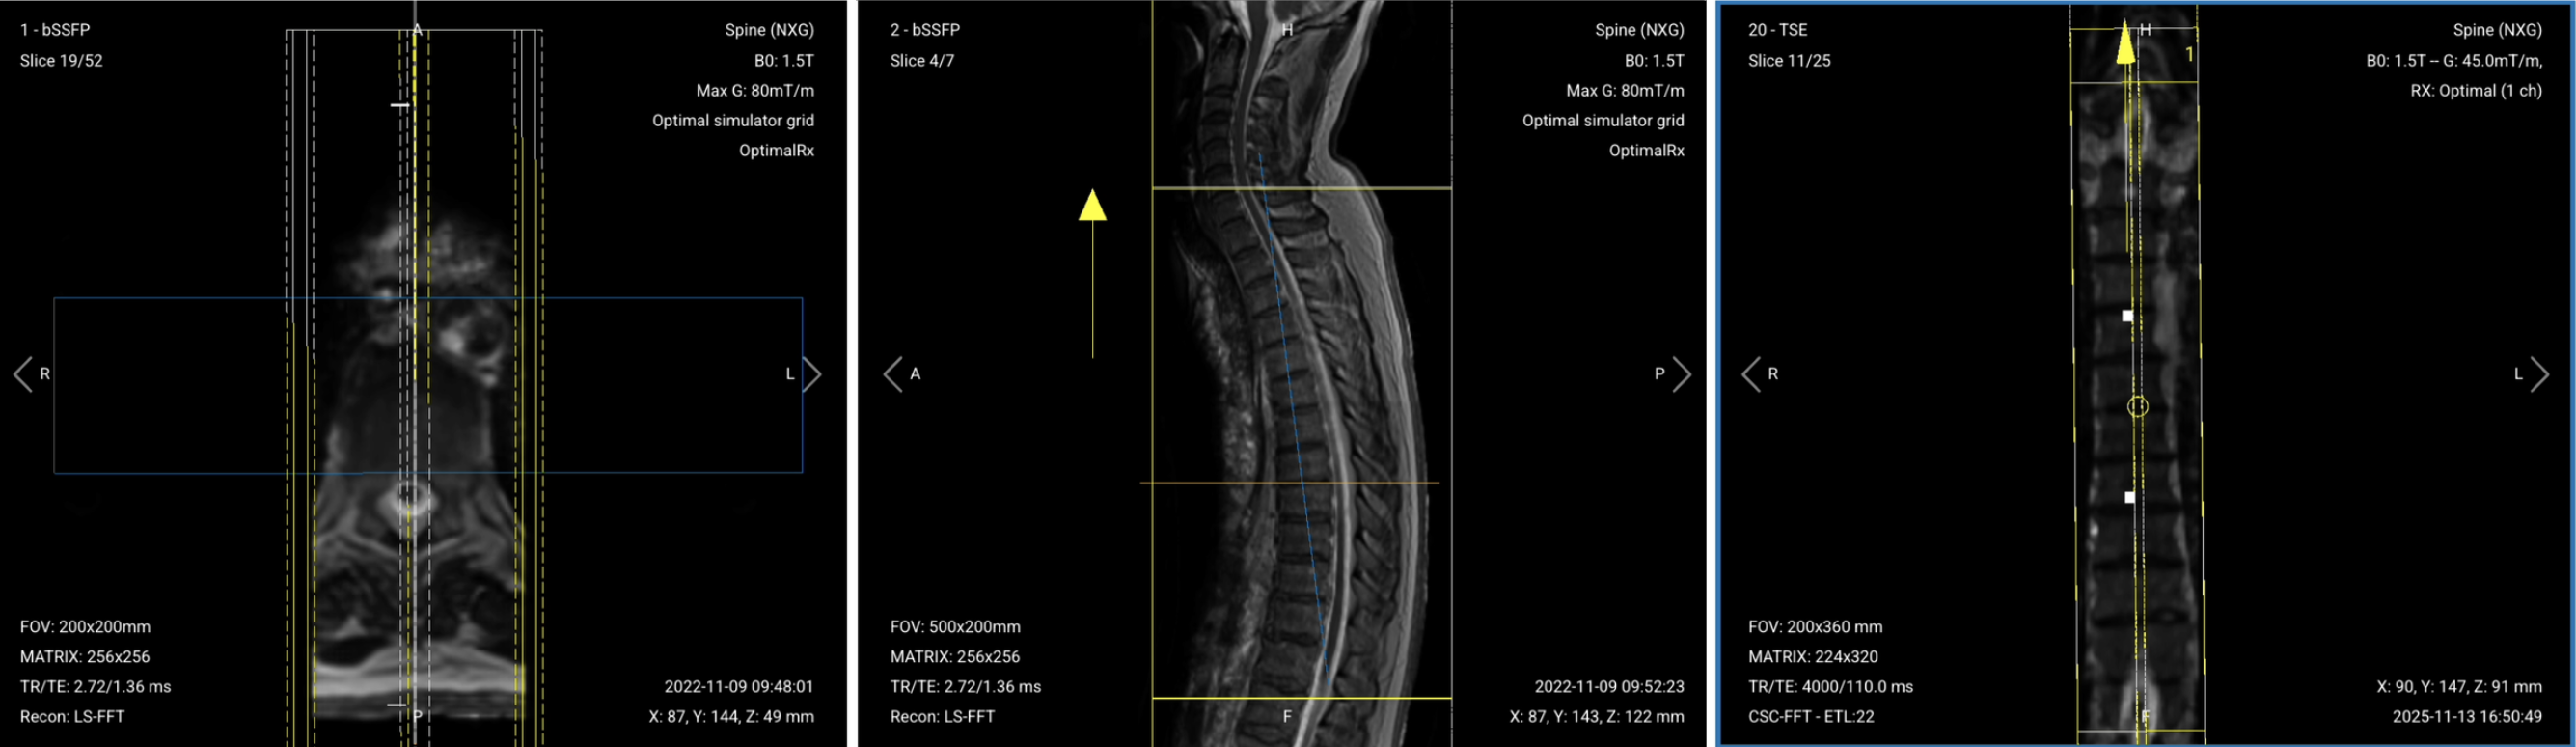

✅ Correct Planning:

Planning Instructions:

Parameters for Sagittal T2 TSE:

| Parameter | Recommended Values | Why These Values |

|---|---|---|

| Echo Time (TE) | 100–120 ms | Longer TE is required for T2 contrast. |

| Repetition Time (TR) | 4,000–6,000 ms | Longer TR is required for T2 contrast. |

| Field-of-View (FOV) | 200 × 340 mm | Rectangular FOV optimized for the thoracic spine's vertical extent, covering superior-to-inferior while minimizing anterior-posterior to reduce scan time. |

| Matrix | 224 × 320 | Medium matrix size provides sufficient resolution while maintaining short scan time and high SNR. |

| Foldover Direction (Phase) | Foot-to-Head (FH) / Superior-to-Inferior | Aligns with cerebrospinal fluid flow to reduce flow artifacts. |

| Number of Slices | 14–18 | Enough slices to cover the thoracic spine from right to left. |

| Slice Thickness | 4 mm | Medium thickness provides good resolution without sacrificing scan time or SNR. |

| Slice Gap | 0.4 mm | 10% of slice thickness prevents crosstalk while ensuring continuity. |

| NEX / Averages | 1–2 | Provides enough SNR while keeping scan time short. |

| Turbo Factor / ETL | 16–24 | Higher turbo factor enhances T2 contrast and reduces scan time. |

| Bandwidth | 50,000 Hz | Medium bandwidth balances SNR with chemical shift artifact reduction. Lower than typical values to improve SNR in the challenging thoracic region. |

| Fold-over Suppression | Yes | Prevents aliasing or wrap-around artifacts. |